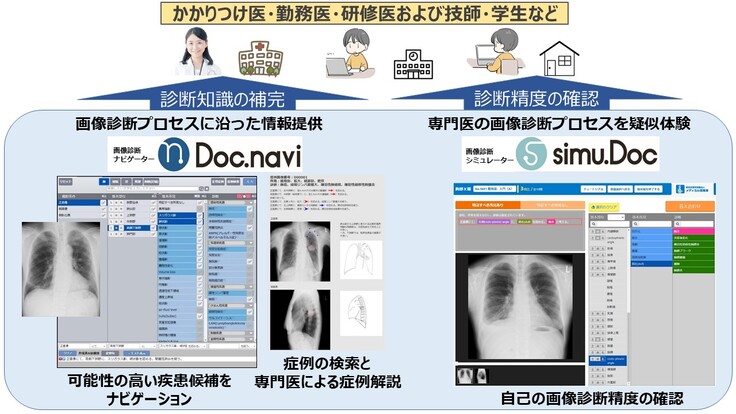

その成果を利用して開発したメディカル指南車の”画像診断ナレッジサービス「読影指南」”は、「専門医」以外の医師や診療放射線技師に対して効率的に画像診断の精度向上をサポートできるサービスを提供します(下図)。画像診断ナレッジサービス「読影指南」は、単に特定の疾患の症例を理解するだけではなく、体系的に画像診断を理解して臨床現場で応用することができるこれまでにないサービスです。

現在、”画像診断ナレッジサービス「読影指南」”は画像診断の精度向上に対する優位性が認められ、採用施設が増えつつあります。すでに”画像診断ナレッジサービス「読影指南」”を導入している兵庫県立加古川医療センターでは、研修医の臨床経験を補う目的でご利用いただいています。一方、診療放射線技師を養成している鈴鹿医療科学大学では、3,4年生全員が”画像診断ナレッジサービス「読影指南」”を用いて学習しています。このように既に医師や技師の育成にお使いいただいている施設では大変好評をいただいていますが、この機会に多くの医療機関などに”画像診断ナレッジサービス「読影指南」”を提供して、ひとりでも多くの医師や診療放射線技師の臨床経験を補うことにより画像診断の精度向上に役立てていきたいと考えています。その結果、疾患の早期発見により、患者やその家族の肉体的、経済的、さらには精神的な負担軽減に貢献することがメディカル指南車の願いです。

しかしこれまでは画像診断の習得は指導する立場の「専門医」や「指導医」が臨床現場で直接指導するのが主流でした。テレワークが叫ばれている昨今でも従来の指導方法にこだわり、オンラインサービスでの画像診断の精度向上には否定的な意見があります。その理由の一つに、過去に提案されてきたようなサービスでは画像診断の精度向上には不十分であったことがあげられます。しかし”画像診断ナレッジサービス「読影指南」”は、コンピュータ(AI)が「専門医」に代わって画像診断の精度向上をサポートし、その成果を記録して客観的に把握することができるこれまでにはないサービスです(下図)。ところがその知名度や理解度は十分ではありません。そこでこのサービスを広く知っていただくための情報発信を強化する必要があります。まずは皆様のご支援を、普及促進のための広報宣伝活動の費用の一部として利用させていただきたいと考えています。